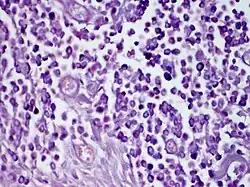

Solitary mastocytoma.

Solitary mastocytoma, also known as cutaneous mastocytoma, may be present at birth or may develop during the first weeks of life, originating as a brown macule that urticates on stroking.[1]: 615  Solitary mastocytoma is a round, erythematous, indurated lesion measuring 1-5 cm in diameter. It can be mildly itchy or asymptomatic and develops over time. Predilection is the head and neck, followed by the trunk, extremities, and flexural areas.

Solitary mastocytoma usually presents as an indurated, erythematous, round or oval, yellow-brown or reddish-brown, papule, plaque, or nodule, typically measuring 1 to 5 cm in diameter.[2] The lesion frequently has a leathery or rubbery nature and a peau d'orange (pebbly, orange peel-like) appearance.[3] The margins of the lesions may be sharp or vague.[4] The degree of pruritus varies; a lesion may be mildly itchy or asymptomatic.[5] It normally develops larger for a few months, then for a variable amount of time grows in accordance to the patients size before gradually shrinking.[3] The head and neck are the sites of predilection, followed by the trunk, extremities, and flexural areas.[6] Usually, the soles and palms are unaffected.[7]

The lesion may urticate on its own initiative or, more frequently, in response to being stroked or rubbed. The lesion becomes itchy, erythematous, or edematous when touched or rubbed; this reaction is known as the Darier sign.[3][8] The phenomenon is regarded as pathognomonic since it is brought on by the release of mast cell mediators in response to physical stimulus.[9] The diagnosis of mastocytosis is not ruled out in the absence of a positive Darier sign because it is evoked in only around 50% and 90% of patients with solitary mastocytoma and other kinds of cutaneous mastocytosis, respectively.[10][11] Certain lesions may erupt in painful blisters.[4][12]

Based on the lesion's shape, the existence of a positive Darier sign, and the lack of systemic involvement, the diagnosis is primarily clinical.[19] If necessary, a skin biopsy can be used to confirm the diagnosis by demonstrating a KIT mutation in the lesional skin and confirming mast cell infiltration in the dermis.[2]